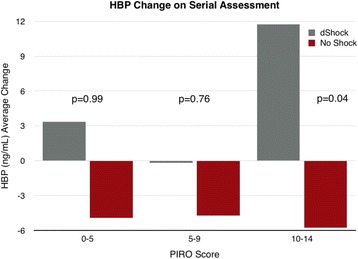

P020 - Impact of disease severity assessment on performance of heparin-binding protein for the prediction of septic shock

R. Arnold, M. Capan, A. Linder, P. Akesson